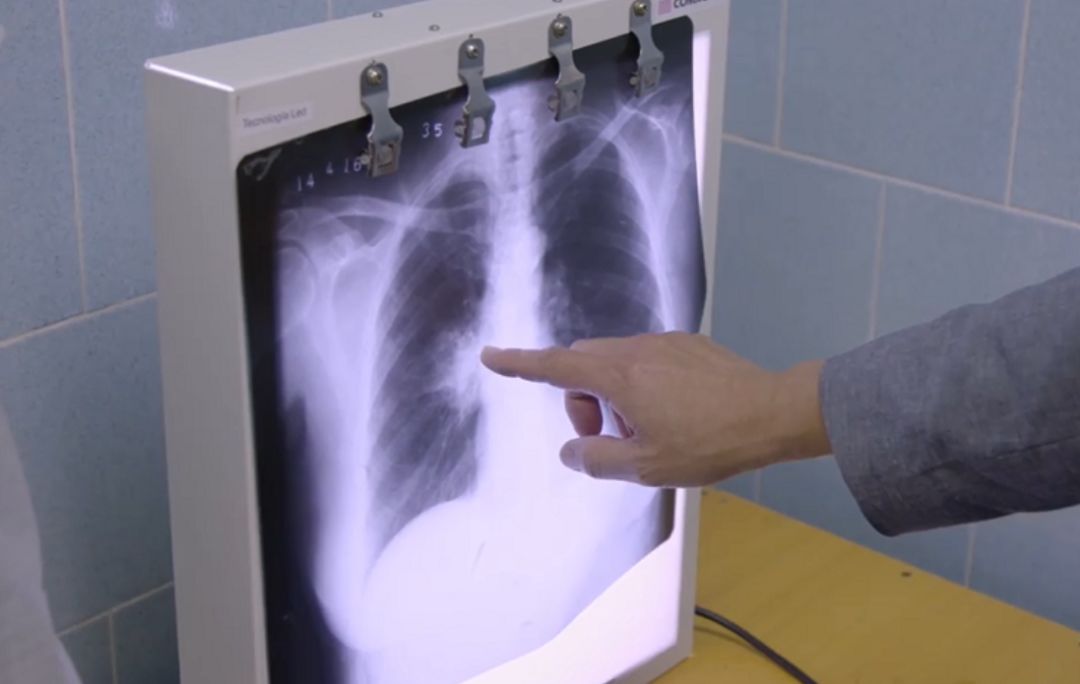

2017年,塞尔维亚人Dejan Babic突然出现了咳嗽,他去医院做了血液检查,看看是否有感染,结果却发现他的血沉异常的高,于是医生建议他做个腹部的B超和肺部的X线,结果却发现他的肺上有个病灶。

令医生惊叹的是,疫苗治疗6个月后,Magaly的肺部X光片显示肿瘤已经不见了。